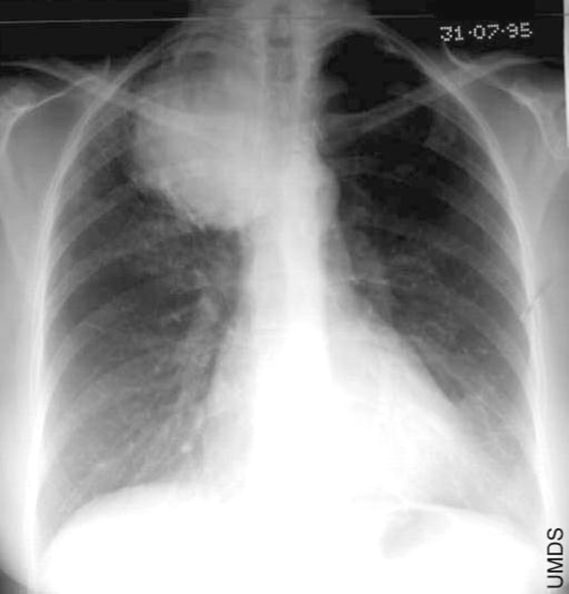

This patient has a history of left mastectomy; what should you be cautious about when interpreting this CXR?

R breast accentuates pulmonary vessels at base of R lung — with mastectomy history, these accentuations can be mistaken for RLL infiltrates & the darker left lung can be misinterpreted as hyperinflation.